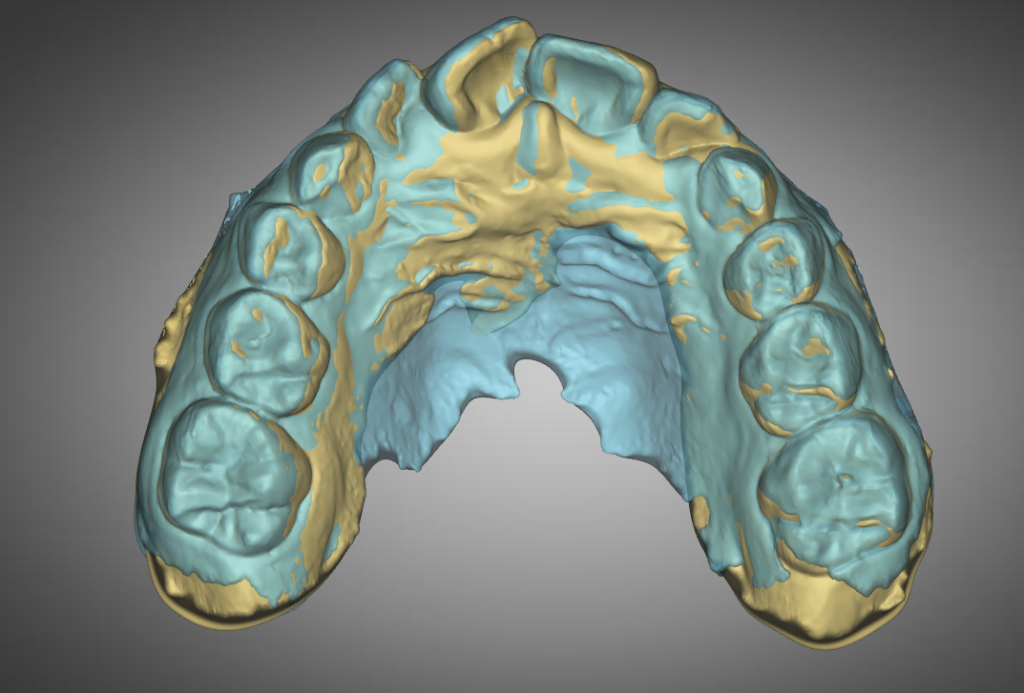

- YELLOW = Initial 2022-10-29

- BLUE = 2nd Review2023-05-30

Second quarter has signs of better compliance with evidences of expansion bilaterally as seen by the blue on the buccal(cheek) sides of the posterior teeth.